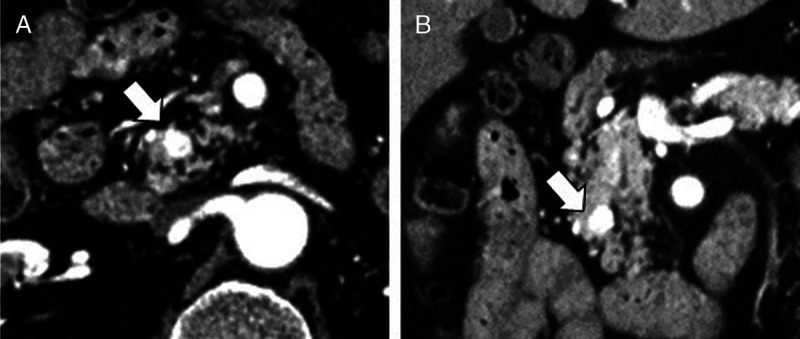

Hormonal changes revealed by selective arterial calcium injection tests in patients with insulinoma treated with EUS-guided ethanol injection.

{"title":"Hormonal changes revealed by selective arterial calcium injection tests in patients with insulinoma treated with EUS-guided ethanol injection.","authors":"Kazuyuki Matsumoto, Motoshi Komatsubara, Kenichi Inagaki, Hironari Kato, Motoyuki Otuka","doi":"10.1097/eus.0000000000000058","DOIUrl":null,"url":null,"abstract":"","PeriodicalId":11577,"journal":{"name":"Endoscopic Ultrasound","volume":"13 3","pages":"193-195"},"PeriodicalIF":5.4000,"publicationDate":"2024-05-01","publicationTypes":"Journal Article","fieldsOfStudy":null,"isOpenAccess":false,"openAccessPdf":"https://www.ncbi.nlm.nih.gov/pmc/articles/PMC11419466/pdf/","citationCount":"0","resultStr":null,"platform":"Semanticscholar","paperid":null,"PeriodicalName":"Endoscopic Ultrasound","FirstCategoryId":"3","ListUrlMain":"https://doi.org/10.1097/eus.0000000000000058","RegionNum":1,"RegionCategory":"医学","ArticlePicture":[],"TitleCN":null,"AbstractTextCN":null,"PMCID":null,"EPubDate":"2024/5/31 0:00:00","PubModel":"Epub","JCR":"Q1","JCRName":"GASTROENTEROLOGY & HEPATOLOGY","Score":null,"Total":0}